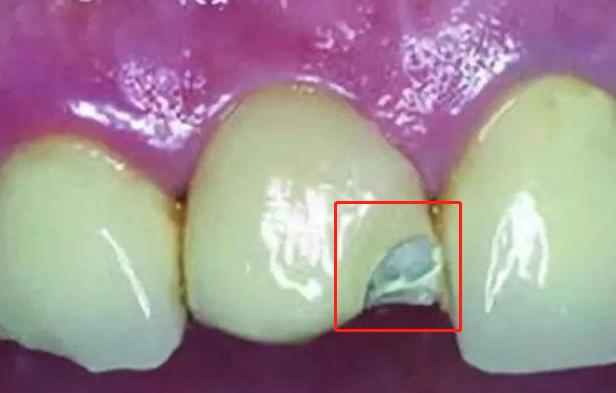

突然间崩瓷了

所谓崩瓷,就是在佩戴烤瓷牙的一段时间后,烤瓷牙突然掉了一块,严重影响美观,在崩瓷之后,烤瓷牙内部金属外露,时间久了会与口腔中的唾液食物残渣产生化学反应,影响身体健康,不仅如此,在烤瓷牙崩瓷之后,有时还产生内部刮伤流血现象,所以如果有一天你的烤瓷牙崩瓷了,那么就意味着它宣布下岗了,不必再挽留了,否则受伤生病产生牙齿疼痛的都是你在承受。